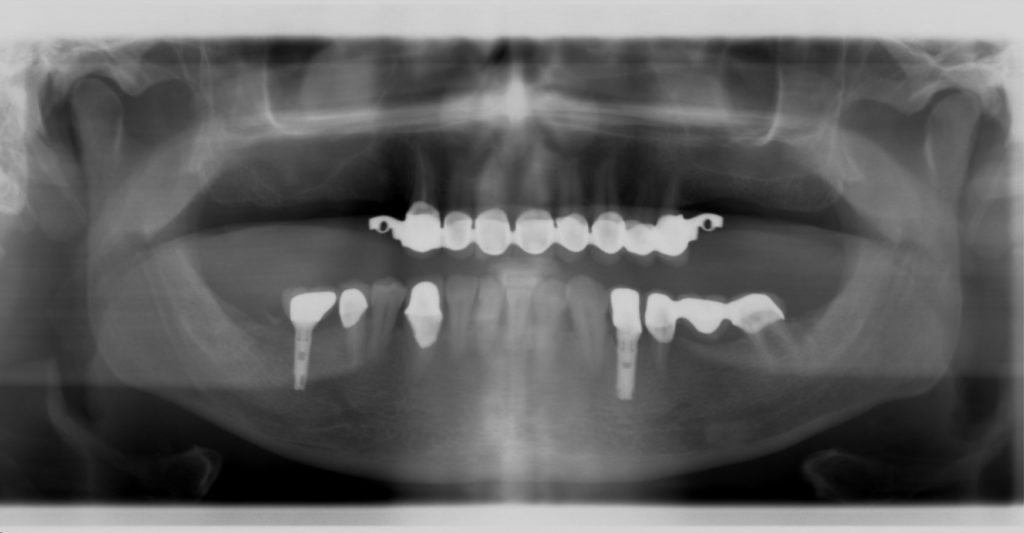

First panoramic radiograph (initial condition) presented by the patient.

Follow-up panoramic radiograph following installation of the lower implants and removal of the lower left wisdom tooth.

Follow-up radiograph of the finished replacements: hidden-clasp metal-ceramic bridge in the maxilla, and fixed metal-ceramic crowns and bridges borne by natural teeth and implants in the mandible.